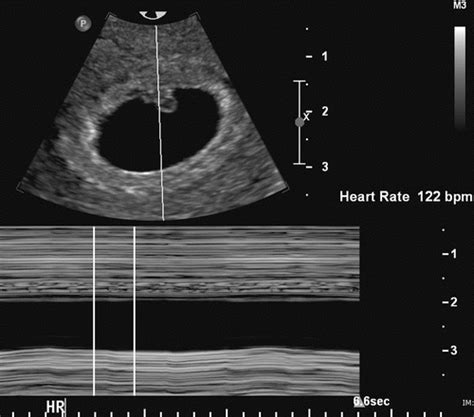

The normal fetal heart rate (FHR) is a crucial indicator of fetal well-being during pregnancy. A normal FHR typically ranges from 110 to 160 beats per minute (bpm), with an average rate of around 140 bpm. This range can vary slightly depending on the gestational age and the individual fetus. It's essential to monitor FHR regularly during pregnancy to detect any potential abnormalities or signs of fetal distress.

- The normal fetal heart rate ranges from 110 to 160 beats per minute (bpm), with an average rate of around 140 bpm.

Fetal heart rate can vary depending on gestational age. During early pregnancy, the fetal heart rate is typically faster, ranging from 160 to 200 bpm. As the pregnancy progresses, the fetal heart rate slows down, reaching a range of 110 to 160 bpm by around 20 weeks gestation. Understanding these changes is crucial for accurate fetal heart rate monitoring and interpretation.

| Early pregnancy (6-8 weeks) | 160-200 bpm |

| Mid-pregnancy (12-18 weeks) | 140-160 bpm |

| Late pregnancy (20-40 weeks) | 110-160 bpm |